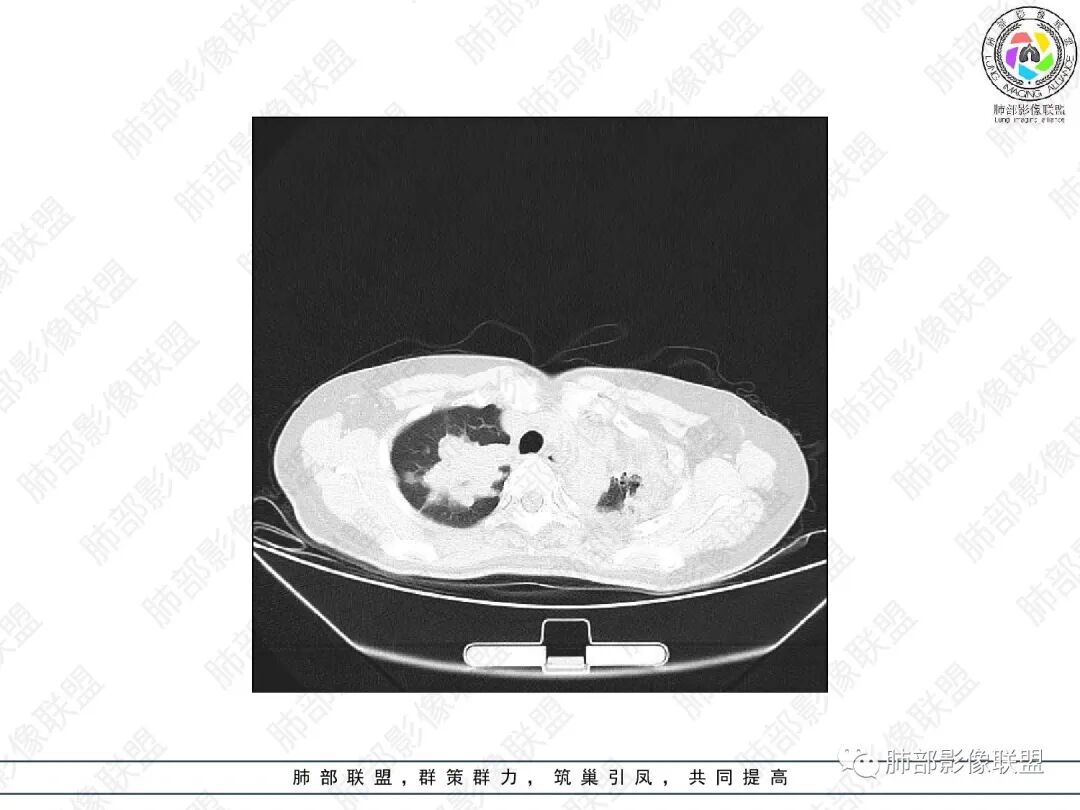

1.中年女性,主因“咳嗽、咳痰半年余”入院,既往史:8年前因左肺病在外院变行左肺叶切除术,诉术后抗结核治疗1年,具体病理等不详。实验室IGE显著增高。

2.胸部CT:右肺上叶及中叶不规则块状影,沿支气管走行方向指套样影,支气阻塞湖嵌塞,腔内可见高密度影。灶周可见磨玻璃,外围见结节影及树芽征。左肺体积缩小,见不规则条索影、胸膜增厚,纵隔牵拉左移。

3.综合分析:结合患者病史及胸部CT主要鉴别ABPA(右肺上叶不规则块影,指套样顺延支气管方向,抗结核治疗1年,肺部病灶仍明显)及继发性肺结核TB(右肺上叶不规则肿块,其可见高密影,边缘模糊,周围卫星灶、树芽征,沿支气管爬行)。